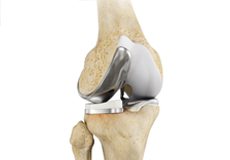

Total Knee Replacement

Total knee replacement, also called total knee arthroplasty, is a surgical procedure in which the worn out or damaged surfaces of the knee joint is removed and replaced with an artificial prosthesis.

Knee Implants

Knee implants are artificial devices that form the essential parts of the knee during a knee replacement surgery. The knee implants vary by size, shape, and material. Implants are made of biocompatible materials that are accepted by the body without producing any rejection response. Implants can be made of metal alloys, ceramic or plastic, and can be joined to the bone.